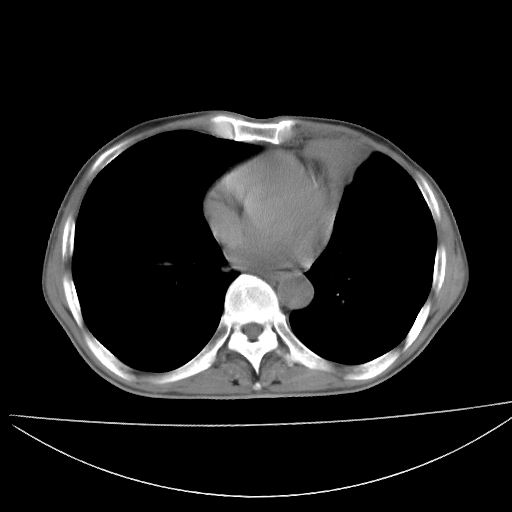

以下是引用杀毒软件在2009-4-28 17:58:00的发言:[br]考虑----左肺慢性肺脓肿形成继发上叶含气不良---抗炎后复查---待排肿瘤所致[br][br][本贴已被 杀毒软件 于 2009-4-28 18:01:26 修改过]